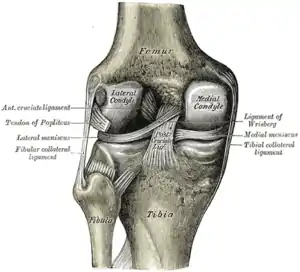

The knee joint is formed by three bones: the femur (thighbone), the tibia (shinbone), and the patella (kneecap). These bones are held together by ligaments, which are strong bands of tissue that keep the joint stable while an individual is walking, running, jumping, etc. There are two types of ligaments in the knee: the collateral ligaments and the cruciate ligaments.

The collateral ligaments include the medial collateral ligament (along the inside of the knee) and the lateral or fibular collateral ligament (along the outside of the knee). These two ligaments function to limit sideways movement of the knee.[6]

The cruciate ligaments form an "X" inside the knee joint with the anterior cruciate ligament running from the front of the tibia to the back of the femur, and the posterior cruciate ligament running from the back of the tibia to the front of the femur. The anterior cruciate ligament prevents the tibia from sliding out in front of the femur and provides rotational stability.[6]

There are also two C-shaped structures made of cartilage called the medial meniscus and lateral meniscus that sit on top of the tibia in the knee joint and serve as cushion for the bones.[1]

| Right knee, front, showing interior ligaments | Left knee, behind, showing interior ligaments |